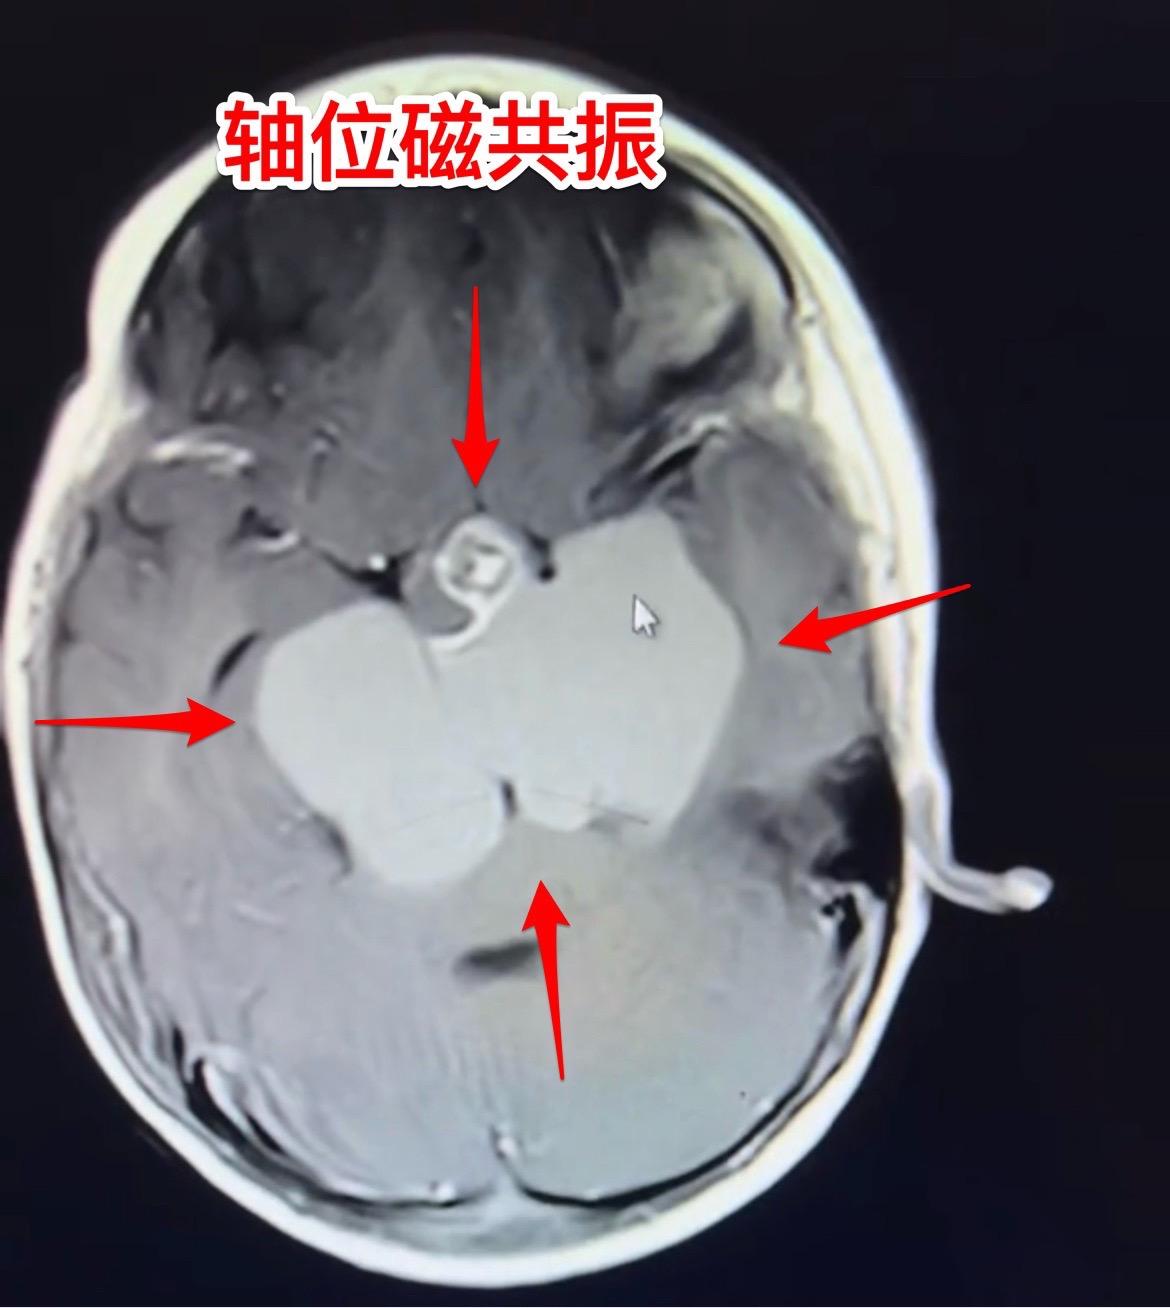

1岁10个月小孩子明天要作手术了。因为视力下降、眼睑下垂发现颅咽管瘤。 肿瘤的大小有多大?观众自己估量一下。 明天要给她作手术了,为她加油!预祝手术成功!